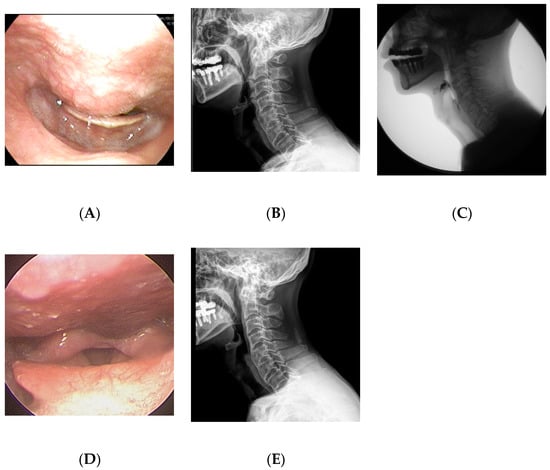

A 65-year-old man visited the department of otolaryngology presenting with dysphagia and odynophagia for 3 months. Although he was able to have an oral diet, he felt severe difficulty in swallowing both solid and liquid food. He complained of a 12-kilogram reduction in body weight due to difficulty swallowing. He had undergone gastrectomy for stomach cancer 13 years ago and was taking psychiatric medications for bipolar disorder. Laryngoscopic examination revealed a protruding mass at the posterior pharyngeal wall obstructing the laryngeal entrance (Figure 2). Lateral cervical radiography and CT revealed a bridging osteophyte at the anterior cervical and thoracic vertebral bodies, suggesting DISH. Preoperative VFSS revealed moderate dysphagia in the oral and pharyngeal phases with incomplete closure of the epiglottis. For solid food, there were large amounts (>50%) of residue at the vallecular pouch and a moderate amount (10–50%) at the pyriform sinus. For liquid, direct aspiration to the trachea was identified. As conservative treatment with a dysphagia diet was not effective, he was referred to the spine center for surgical removal of the osteophyte. The surgery was performed via the modified Smith–Robinson approach and took 50 min with blood loss of less than 50 mL. Bone wax was applied to the bony margin after osteophyte removal. His symptoms markedly improved immediately after the surgery. There was no evidence of regrowth of the osteophyte at 1-year postoperative follow-up.

Figure 2.

A 65-year-old man presented with dysphagia and odynophagia for the past 3 months and 12 kg weight loss. (A) Preoperative laryngoscopy revealed a protruding mass at the posterior pharyngeal wall obstructing the laryngeal entrance. (B) Lateral cervical radiograph showed a bridging osteophyte at the anterior cervical and thoracic vertebral bodies, suggesting DISH. (C) Preoperative visual fluoroscopic swallowing study revealed moderate dysphagia in the oral and pharyngeal phases with incomplete closure of the epiglottis. (D) Postoperative laryngoscopy showed disappearance of the protruding mass at the posterior pharyngeal wall. (E) There was no evidence of regrowth of the osteophyte at 1-year postoperative radiograph.